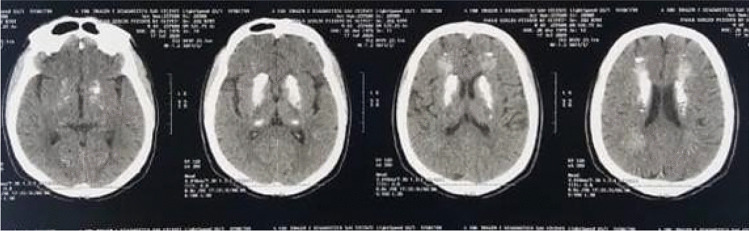

In our research group, we revised the clinical records of a 49-year-old male patient, unvaccinated, with a confirmed laboratory diagnosis of coronavirus disease (immunological diagnosis). In addition, chest computed tomography (CT) evaluation was performed (Fig. 1). The patient presented with seizures, with no known comorbidities, followed by cardiac arrest. The investigation proceeded with neuroimaging that revealed bilateral brain calcifications (as shown in Fig. 2). Unlike the case described by Demir (2020), where ectopic calcinosis was linked to a hormonal etiology, our patient would be diagnosed as having primary or idiopathic brain calcifications. After discharge and follow-up, the patient’s immunization status has changed. Concerning neurological manifestations, he is now asymptomatic.

Fig. 2.

Brain CT showing bilateral brain calcifications